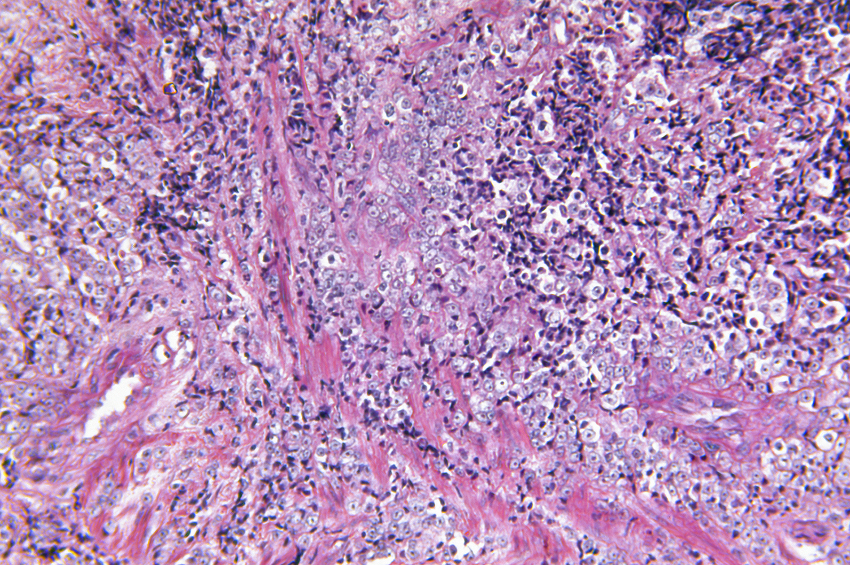

UCSF Helen Diller Family Comprehensive Cancer Center scientists led by Davide Ruggero, PhD, and Kevan Shokat, PhD, used one such drug to stop tumor growth in a mouse model of myc-driven lymphoma and multiple myeloma types of blood cancer.

The researchers targeted mTOR with an experimental drug based on a prototype first designed by Shokat, a chemist and an expert in designing molecules to target this type of protein, called a kinase. In the mice, drug treatment caused a shutdown of excess protein production in myc-driven cancer cells. Myc no longer was able to drive tumor growth, cancer cells committed suicide, and the treated mice survived longer.